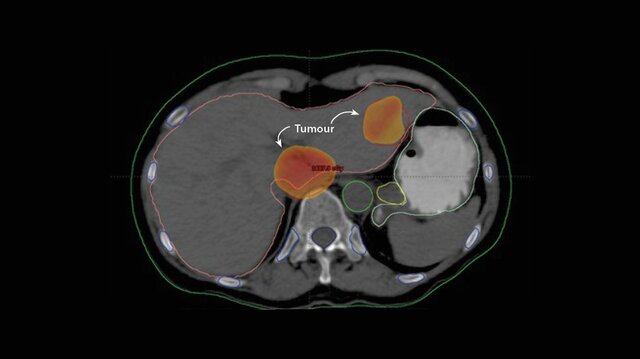

Se usa en la estética, como en cremas para desmanchar la cara y también para la eliminación de tumores, fue un gran invasor para los tumores cancerificos

El análisis de síntomas patológicos de un conjunto de radiólogos, permitió establecer que la incidencia de cáncer en este grupo de trabajo, era significativamente más alta respecto a otros médicos, circunstancia que demostró la peligrosidad de las radiaciones ionizantes y la necesidad de establecer normas específicas de radio protección.

En este año se logra evidenciar que cuando el cuerpo humano es sometido a bajas dosis de radiación o a una dosis mayor pero que es recibida a lo largo de un gran período de tiempo, no existen efectos deterministas apreciables, pero se supone que es posible la existencia de efectos estocásticos, tales como el cáncer o la aparición de enfermedades congénitas.